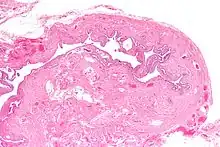

Micrograph of salpingitis isthmica nodosa, showing the characteristic nodular thickening. H&E stain.

Salpingitis isthmica nodosa (SIN), also known as diverticulosis of the fallopian tube, is nodular thickening of the narrow part of the uterine tube, due to inflammation.

It is characterized by nodular thickening of the tunica muscularis of the narrow (isthmic) portion of the fallopian tube. In severe cases, it leads to complete obliteration of the tubal lumen. It is uncommonly bilateral.[2]